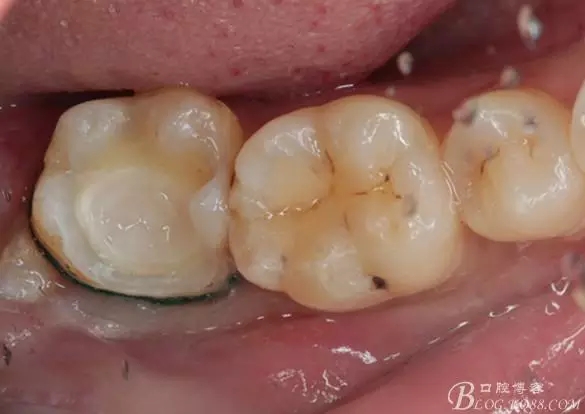

流動樹脂充填窩洞,金霸王車針和鎢鋼車針常規(guī)備牙,配合硅膠尖拋光,頰側(cè)排00排齦線。硅橡膠二次法取模,記錄咬頜關系,臨時樹脂充填窩洞。

一周后復診,37臨時充填物完好。去除臨時充填物,清潔基牙,試戴嵌體,就位良好,邊緣密合。取下嵌體,常規(guī)處理,9.5%HF處理20S,沖洗一分鐘,95%酒精蕩洗5分鐘?;劳磕?7%的磷酸凝膠,釉質(zhì)區(qū)域酸蝕30S,本質(zhì)區(qū)域15S。粘固用的是3M第八代粘接劑套裝,照說明書逐步操作。最終固化時涂滿阻氧劑,每個牙面最少光照30S,光固化燈用漸強模式。常規(guī)調(diào)合,配合硅膠尖套裝拋光。術后常規(guī)醫(yī)囑,不適隨診。